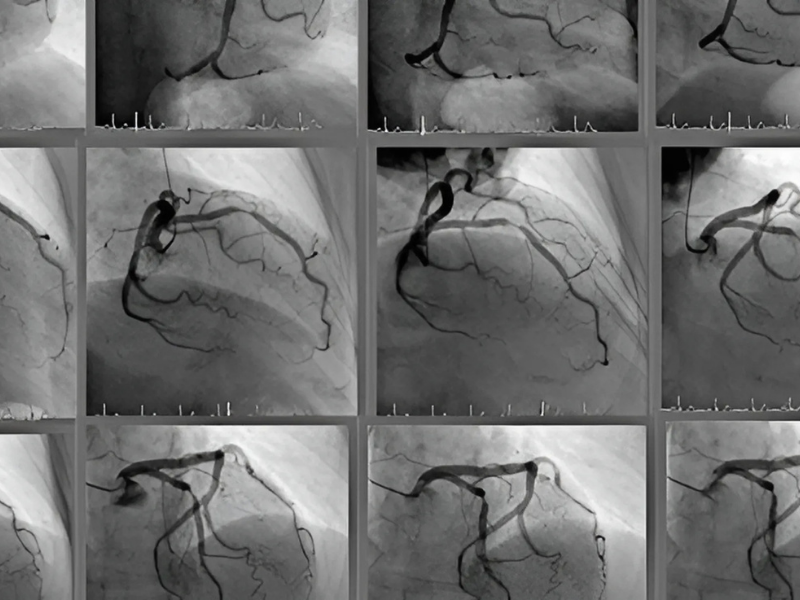

KORONER ANJİOGRAFİ: Koroner anjiografi halen koroner arter hastalığının tanısında altın standart olarak duruyor. Kasık veya koldan yapılabilmektedir. Atar damara bir kateter ile girilerek verilen bir boya ile damarlar görünür hale getiriliyor. Kalp damarlarının anatomisi, darlıkların şekli, daralmanın oranı tespit ediliyor. Daha önce bypass olmuş veya stent takılmış damarların da değerlendirilmesi yapılabiliyor. Koroner anjiografi işleminden sonra hasta aynı gün taburcu edilebiliyor. Aynı şekilde sadece tanı amaçlı değil tedavi amaçlı olarak da kullanılıyor. Bu durumda elbette uygun vakalarda damar balonla genişletilip stent konabiliyor.

Koroner anjiografi sonrası sorun tespit edilen hastalar 3 grupta tedavi ediliyorlar. Bir kısmına ilaç tedavisi yeterli oluyor. Damar tıkanıklığı kritik seviyede ve uygun damarlarda ise stent ile de açılabiliyor. Diğer grup hastaya da koroner bypas ameliyatı uygulanıyor. Bu kararları tabii ki hastaya göre kalp damar cerrahı ve kardiyolog un beraber vermesi gerekiyor.